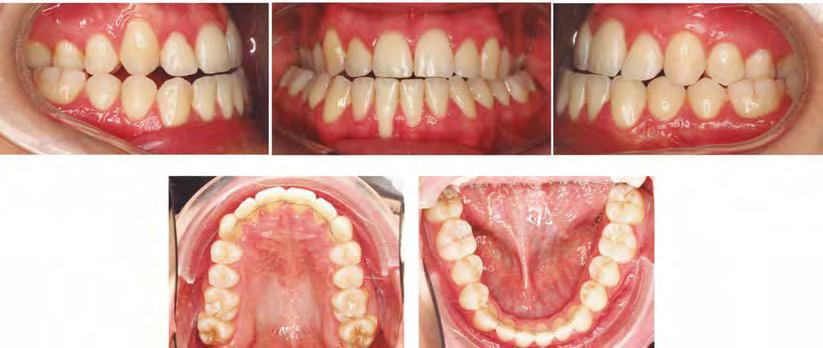

–Uso del anclaje esqueletal como alternativa eficiente en el manejo ortopédico de clases III por deficiencia de maxilar superior, por el Dr. Carlos Becerra y cols. [74]

–MARPE, una alternativa a la disyunción en el paciente adulto, por el Dr. Enrique Solano y cols. [88]